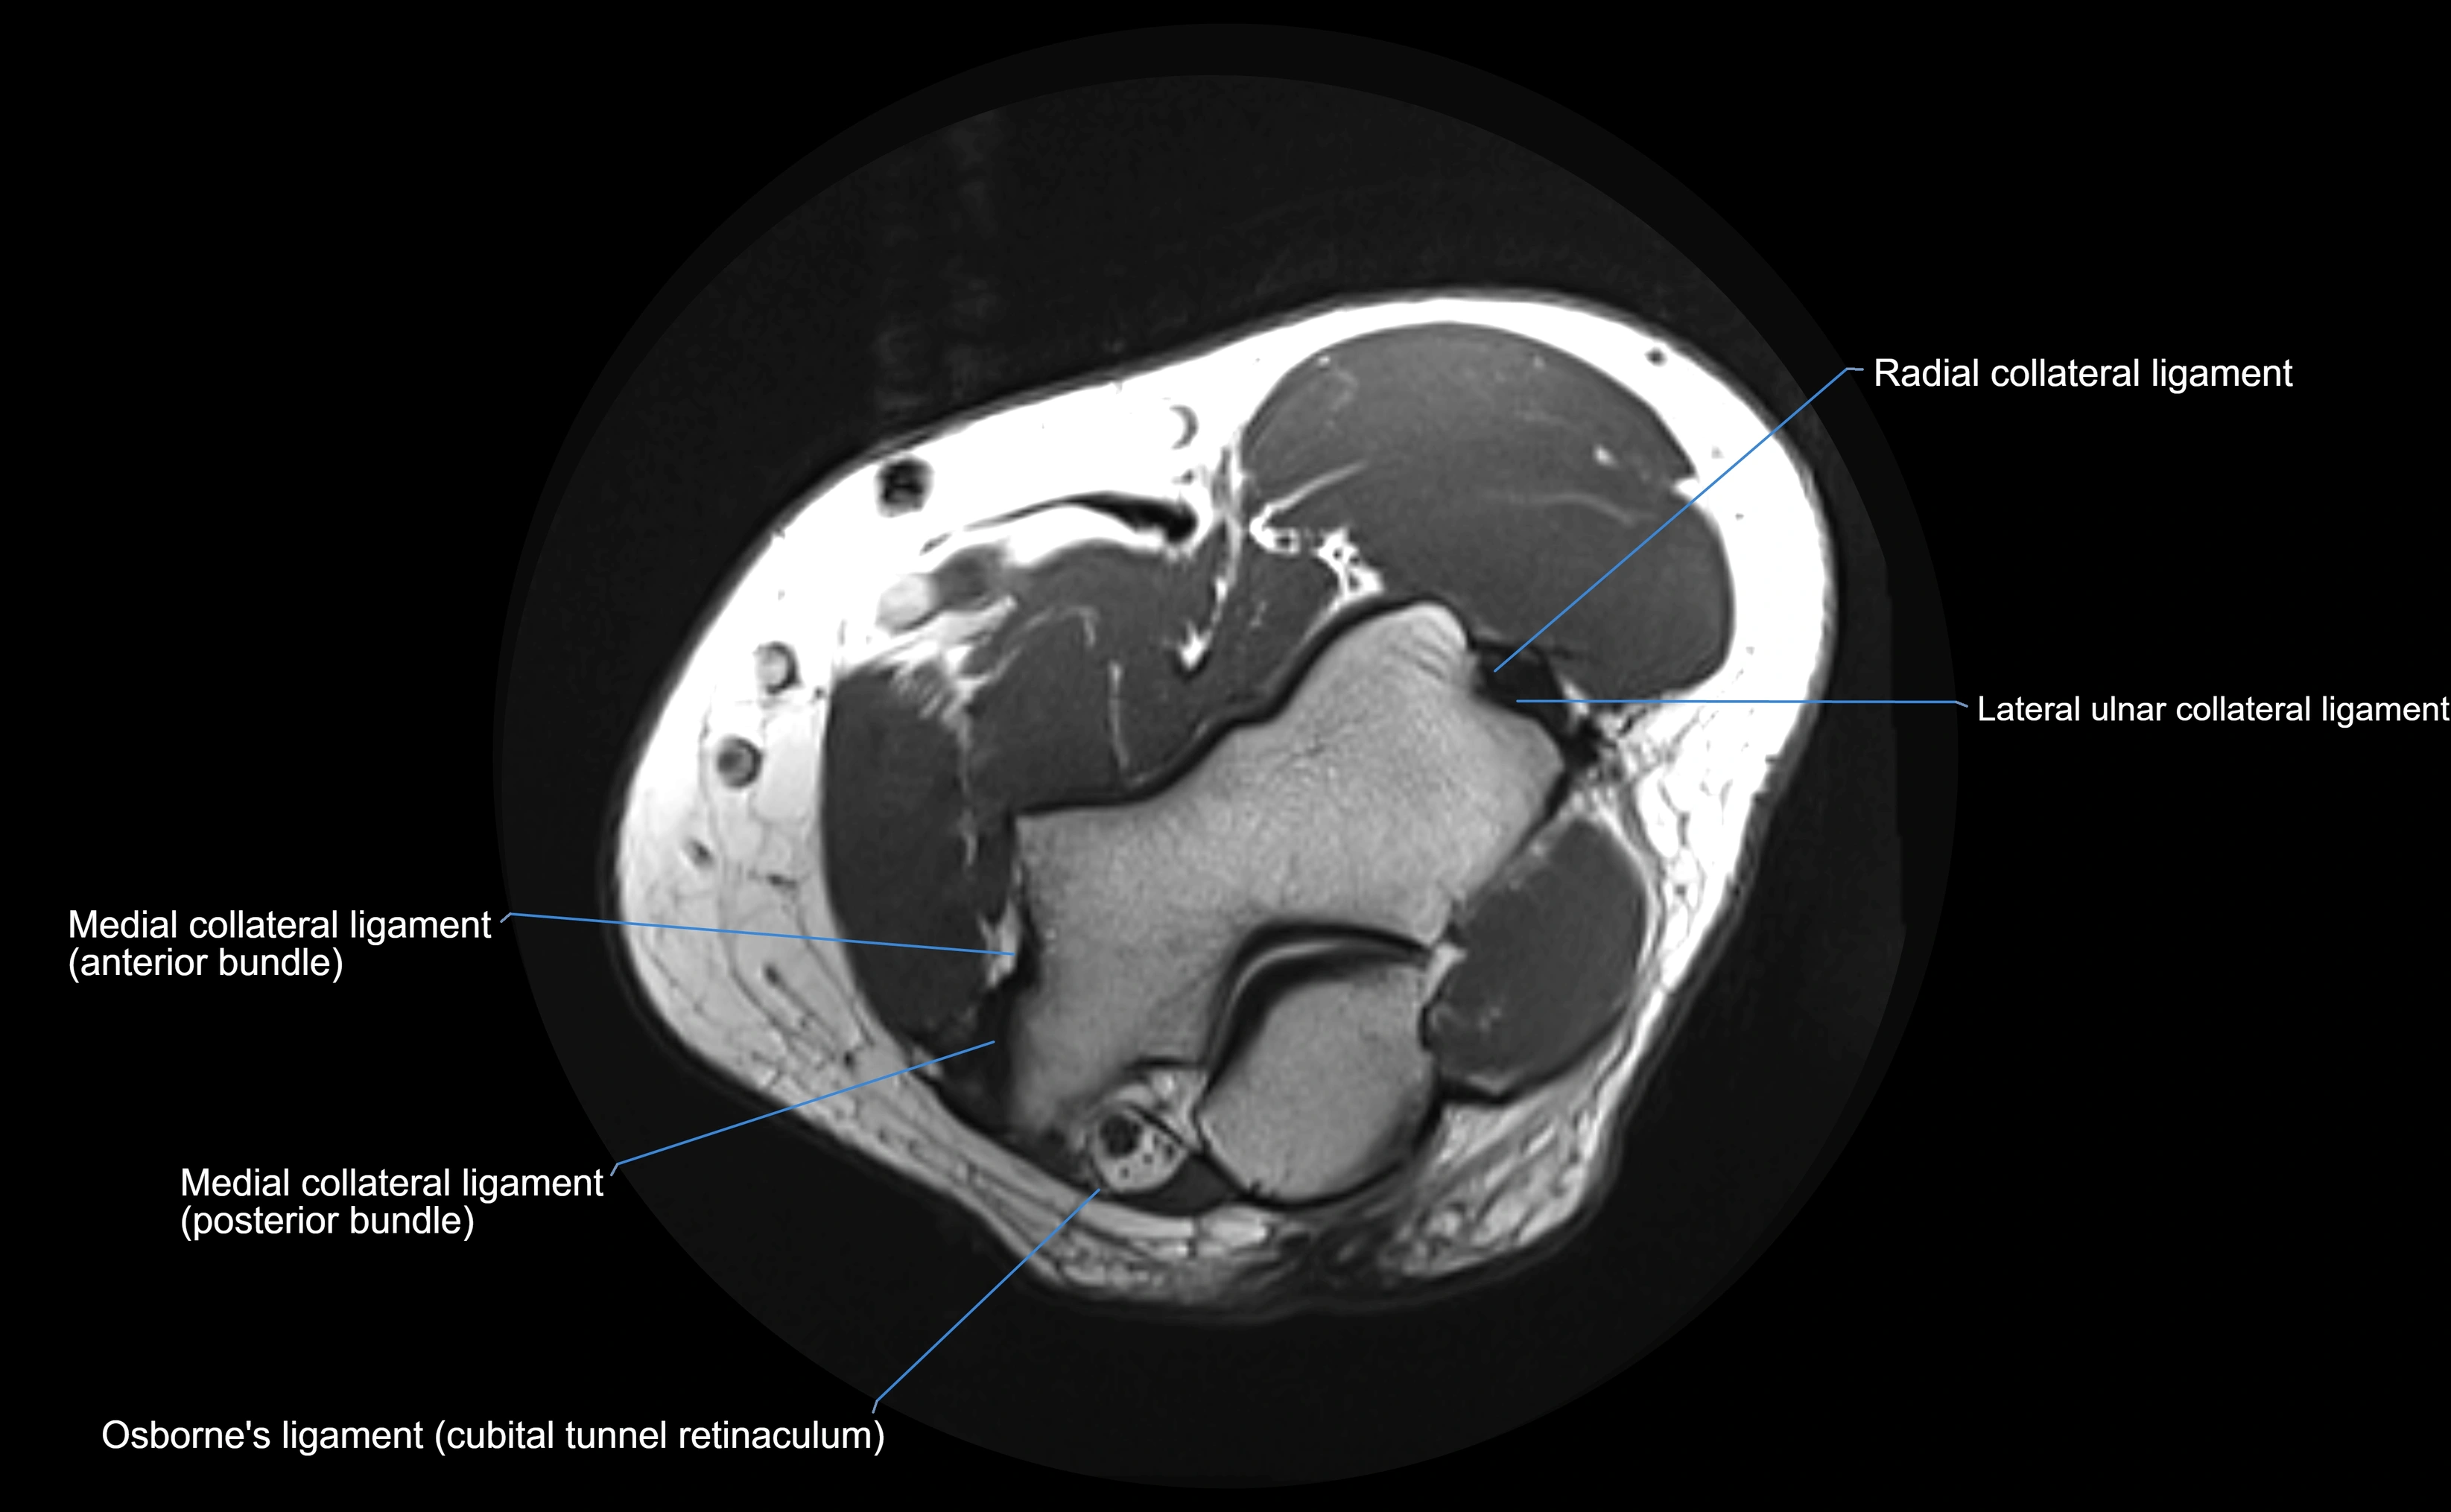

MRI Appearance

T1-weighted images:

• Ligament: low signal intensity (dark), appearing as a continuous band around the radial head.

• Adjacent fat and marrow: bright, creating contrast with the ligament.

• Thickening or disruption indicates injury or fibrosis.

• Joint capsule and synovium seen as thin low-signal lines contiguous with ligament margins.

T2-weighted images:

• Ligament: low signal (dark) with clear delineation from joint fluid.

• Fluid or edema: bright hyperintense, separating or surrounding the ligament in partial tears.

• Complete tear: discontinuity or non-visualization of ligament fibers, often with joint effusion.

MRI images

image